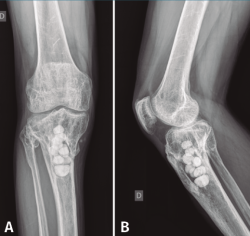

Con el diagnóstico de osteítis crónica de la tibia se realiza desbridamiento óseo y de partes blandas, con posterior plastia de gemelo interno y antibioterapia específica.

Figura 4. Radiografías de frente y de perfil de tibia-peroné donde se objetiva la resección ósea realizada.

En el estudio radiológico posquirúrgico (Figura 4) se puede objetivar la resección ósea realizada.

La evolución posterior fue hacia la resolución del proceso infeccioso.